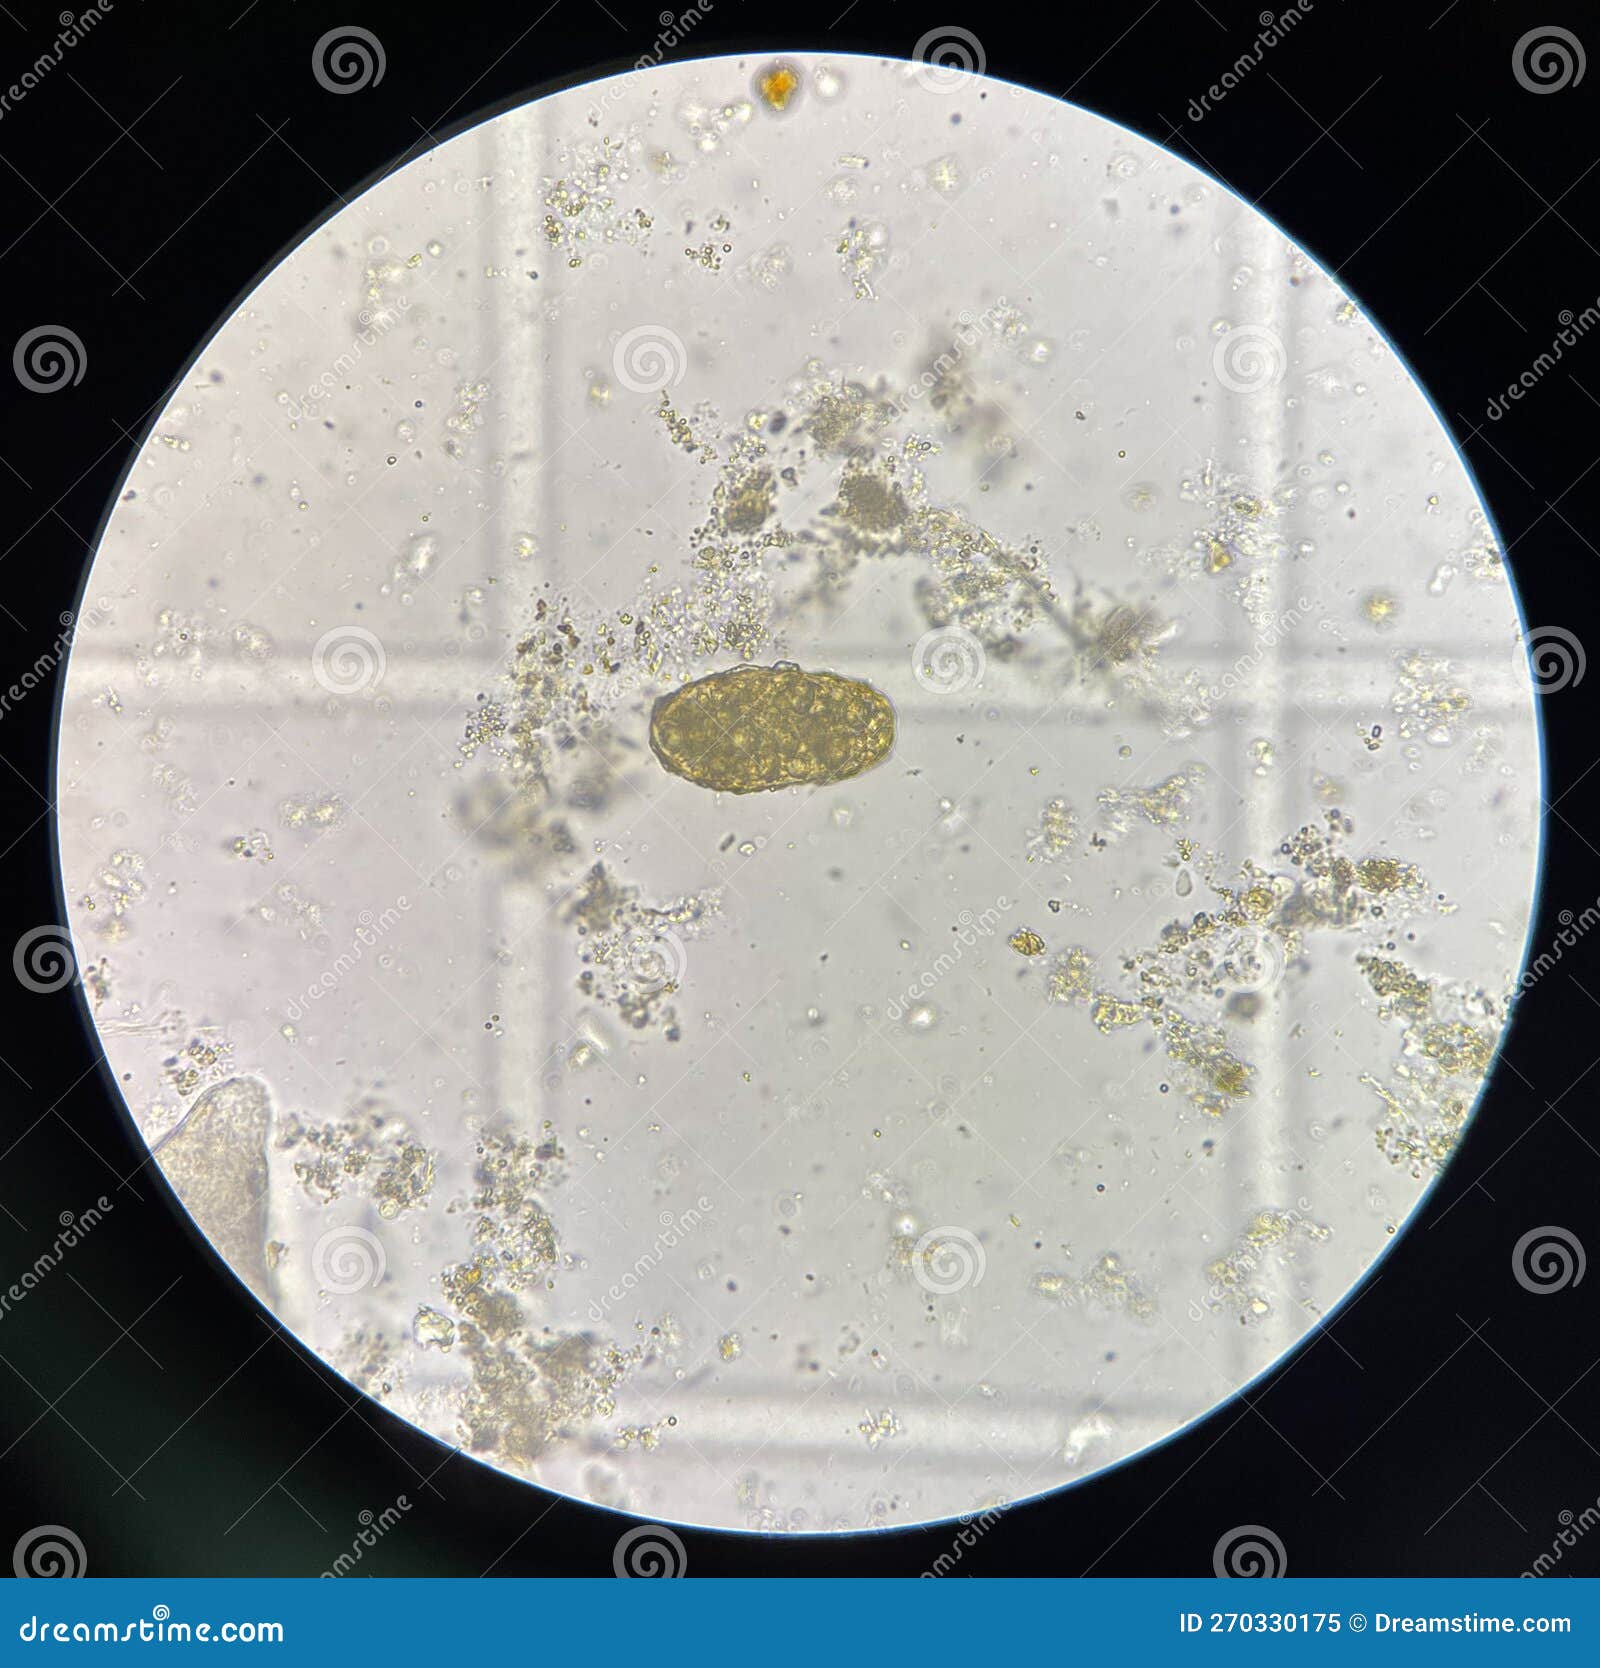

Ascaris Lumbricoides Egg in Stool Exam Stock Photo Image of Stool Examination For Ascariasis ascariasis is concentrated in developing countries of asia, africa, and latin america. stool examination for ova and parasites: Visualization of large, brown 60 µm x 50 µm trilayered eggs is. diagnosis of ascariasis is by microscopic detection of eggs in stool or observation of adult worms in stool or emerging from the. to diagnose ascariasis, your. Stool Examination For Ascariasis.

Stool Examination For Ascariasis . stool examination findings are typically normal in absence of previous infection (during the first 40 d). Visualization of large, brown 60 µm x 50 µm trilayered eggs is. summarize the use of a stool exam to detect ova and parasites in the evaluation of. ascariasis is concentrated in developing countries of asia, africa, and latin america. diagnosis of ascariasis is by microscopic detection of eggs in stool or observation of adult worms in stool or emerging from the. stool examination for ova and parasites: to diagnose ascariasis, your doctor will examine your stool for the tiny (microscopic) eggs and larvae. ascaris lumbricoides is the largest intestinal nematode (roundworm) parasitizing the human intestine and is.

Stool Examination For Ascariasis Visualization of large, brown 60 µm x 50 µm trilayered eggs is. stool examination for ova and parasites: diagnosis of ascariasis is by microscopic detection of eggs in stool or observation of adult worms in stool or emerging from the. ascaris lumbricoides is the largest intestinal nematode (roundworm) parasitizing the human intestine and is. summarize the use of a stool exam to detect ova and parasites in the evaluation of. to diagnose ascariasis, your doctor will examine your stool for the tiny (microscopic) eggs and larvae. Visualization of large, brown 60 µm x 50 µm trilayered eggs is. ascariasis is concentrated in developing countries of asia, africa, and latin america. stool examination findings are typically normal in absence of previous infection (during the first 40 d).